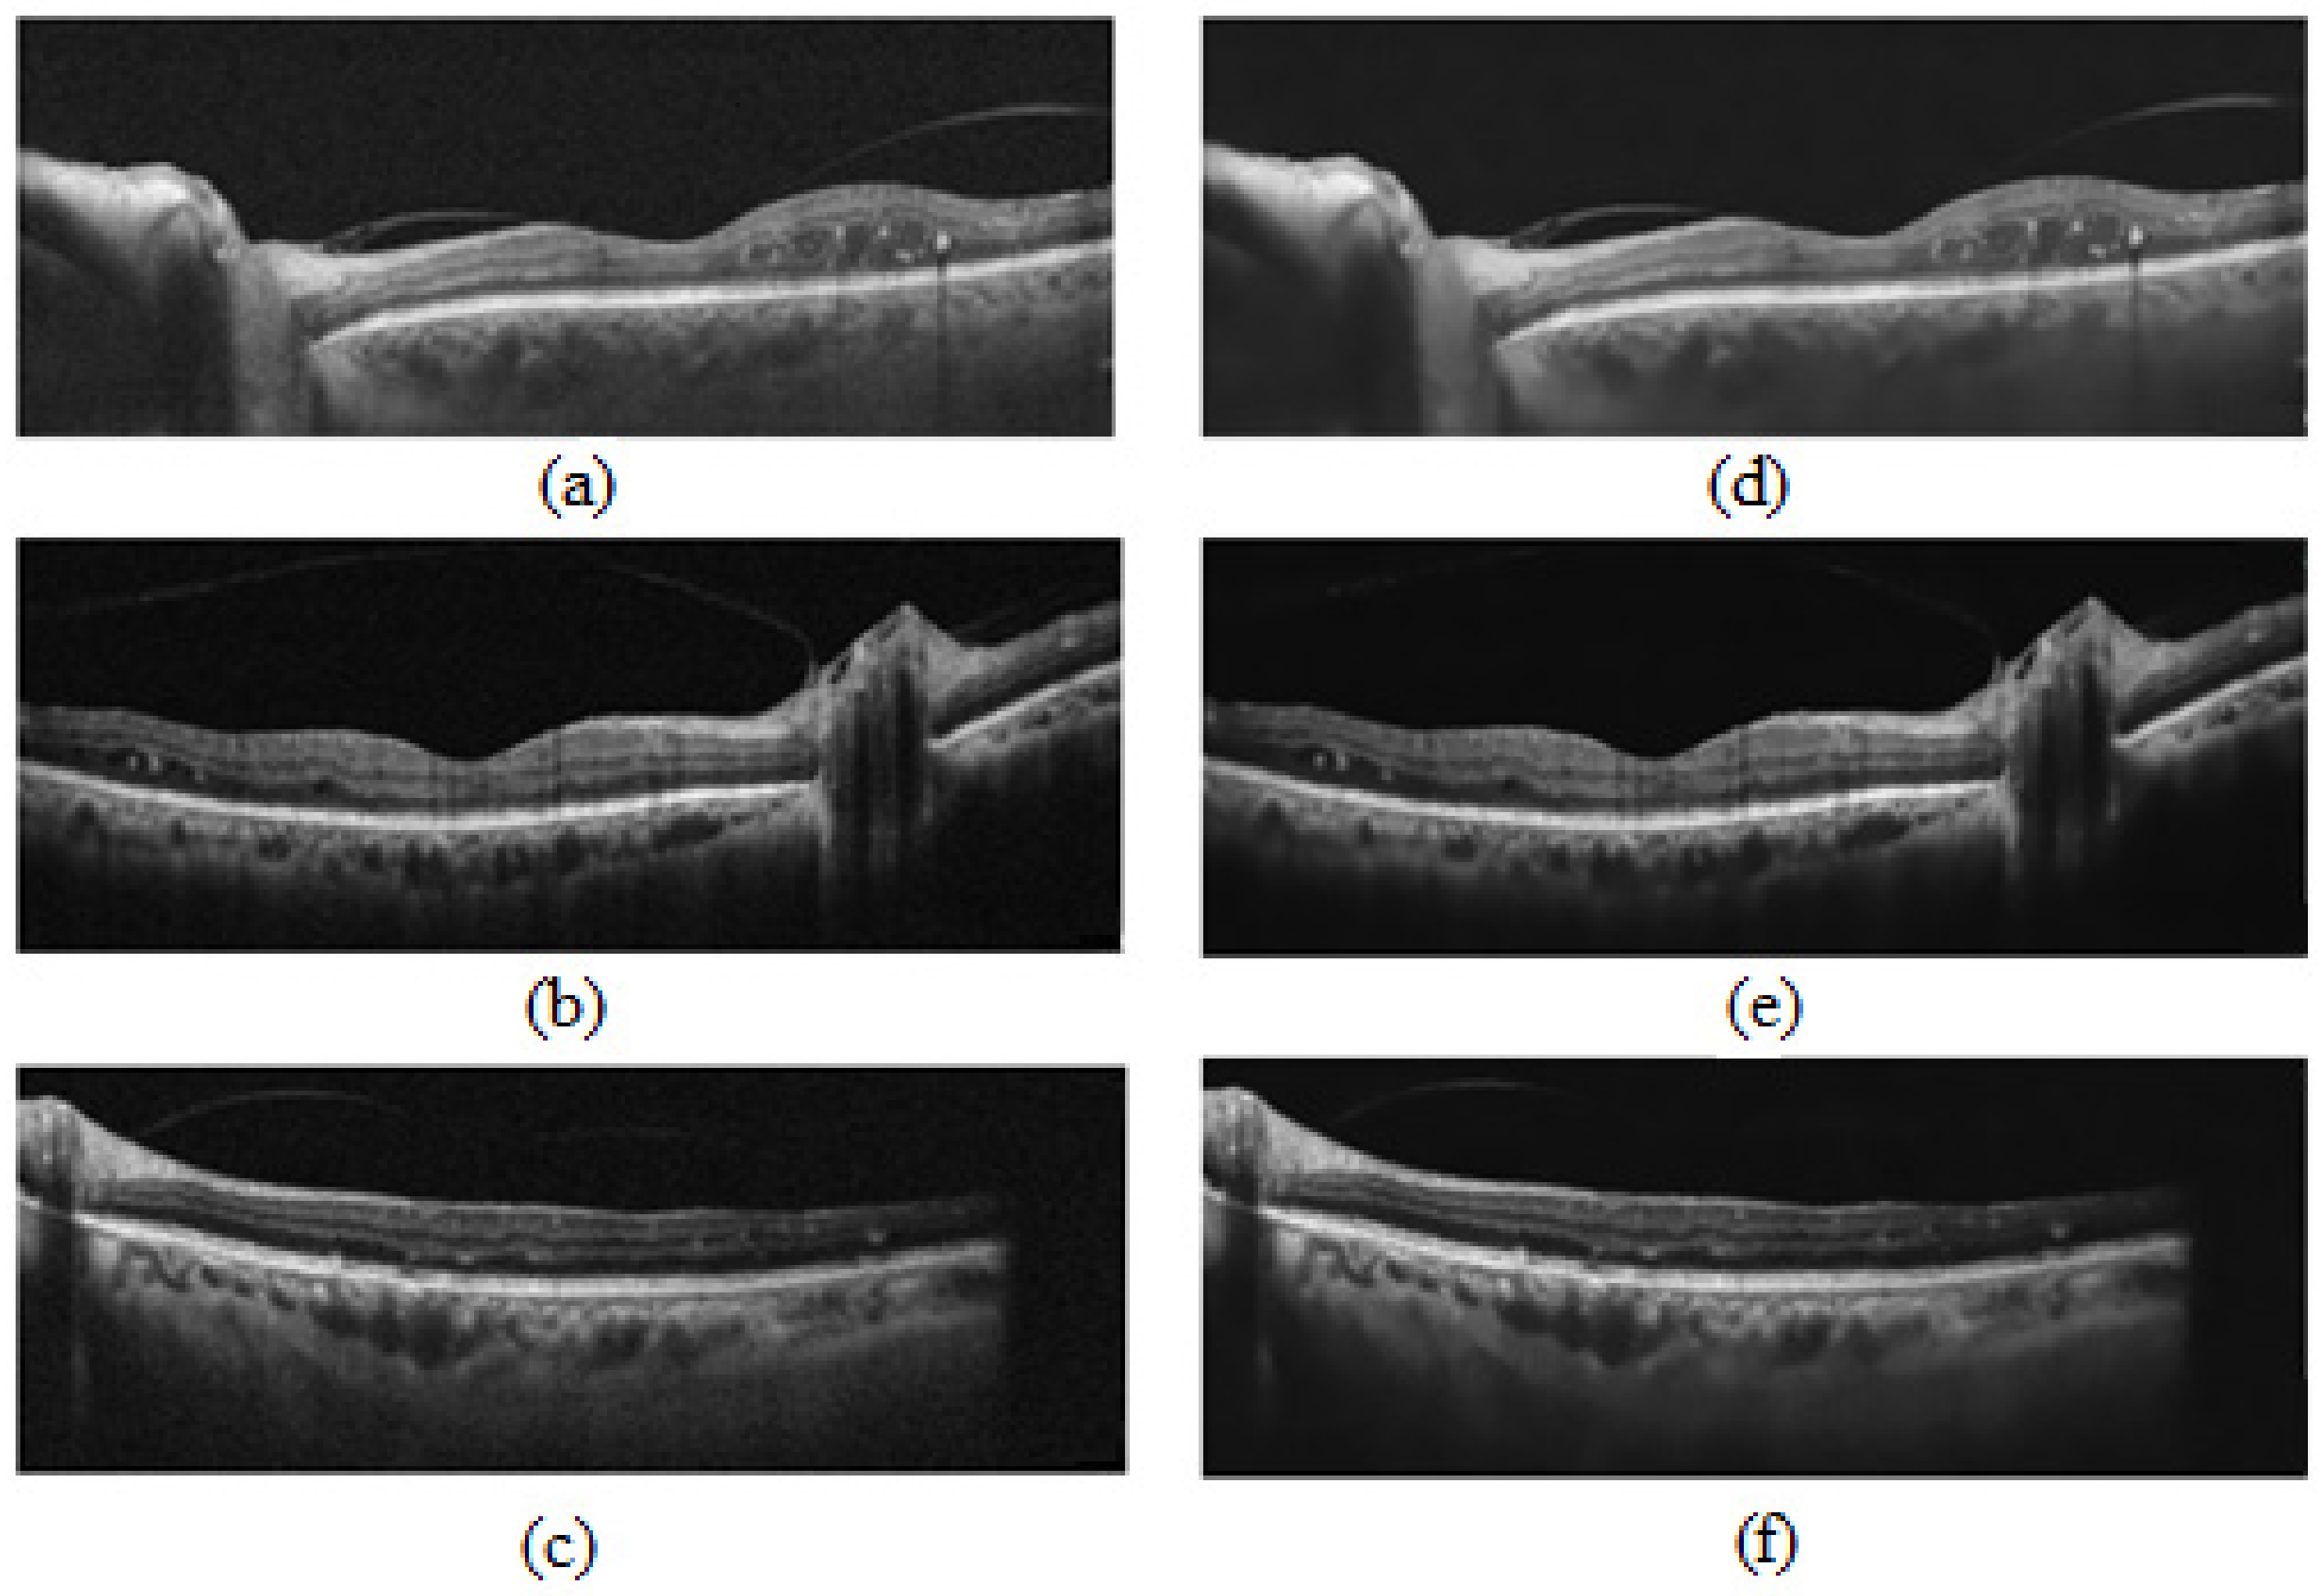

- The proposed modified U-Net segmented the choroid and BM boundaries in challenging cases such as low-contrast images with thickened choroidal areas.

2.1. OCT Data and Manual Annotation

3.1. Choroidal Boundary Segmentation in Pachychoroid Spectrum Dataset

3.2. Choroidal Boundary Segmentation in the Diabetic Retinopathy Dataset